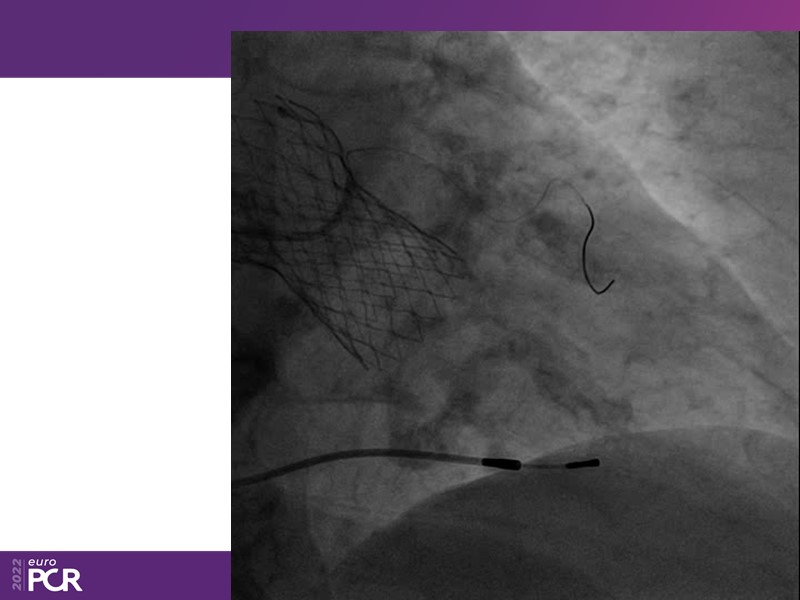

Consult this session to learn how to contribute to streamlined pre- and post-TAVI patient pathways, to discover updates on the optimised TAVI procedure and appreciate the variances in different valve designs and the long-term patient outcomes, as well as to discuss the right time of PCI in TAVI patients (steps on the procedure).